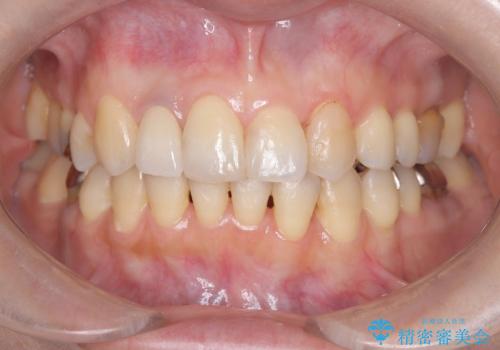

- 「前歯の見た目が気になる」を主訴に来院された患者様です。

失活歯による歯の変色とCR(コンポジットレジン)の劣化による審美不良でした。

オールセラミッククラウンで治療し見た目の改善を行いました。

まず劣化したCRと虫歯を除去した後、仮歯に置き換えました。歯のマージンラインを綺麗に削り光沢が出るまで研磨した後にオールセラミッククラウンの型取りを行っています。